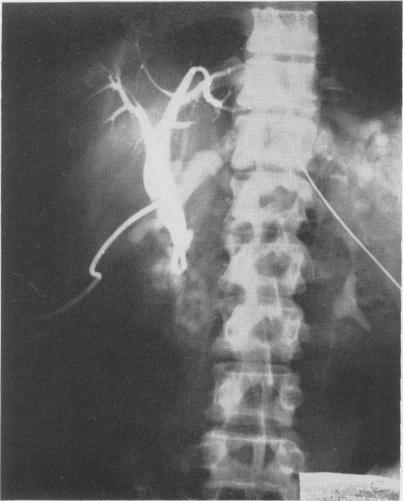

Jaundice due to obstruction of the common duct by aberrant artery: demonstration of celiac anomaly by translumbar aortography and simultaneous choledochogram.

Ann Surg. 1961 Jan;153(1):134-7. doi: 10.1097/00000658-196101000-00015.